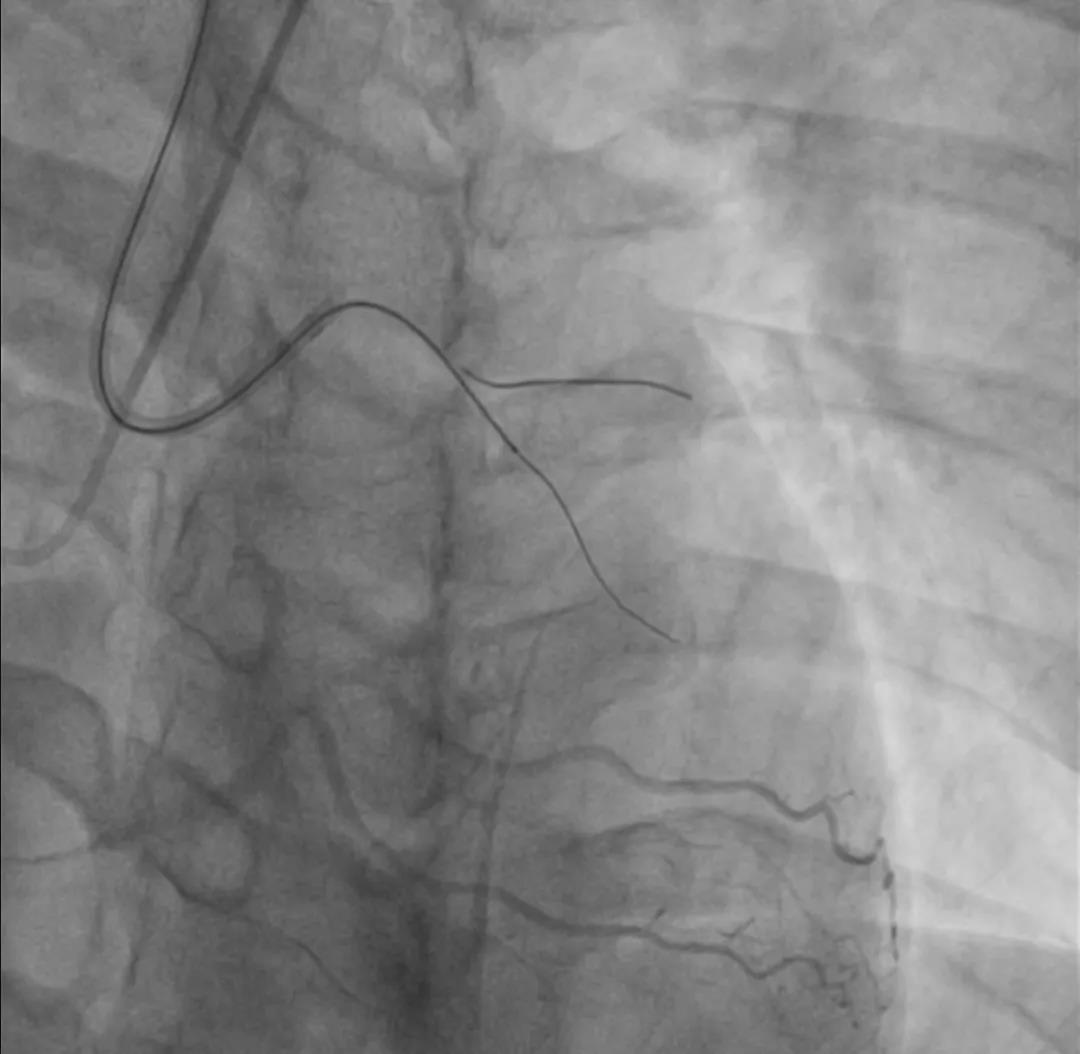

充分预扩

Score flex 2.0*10mm 10atm

Quantum 2.5*20mm 10atm

IVUS-2 预扩张后小夹层和血肿

Dia开口

Dia近段

LAD闭塞段

LAD近段

LAD开口

DEB bingo 2.5*30mm 10atm 结果满意

IVUS-3